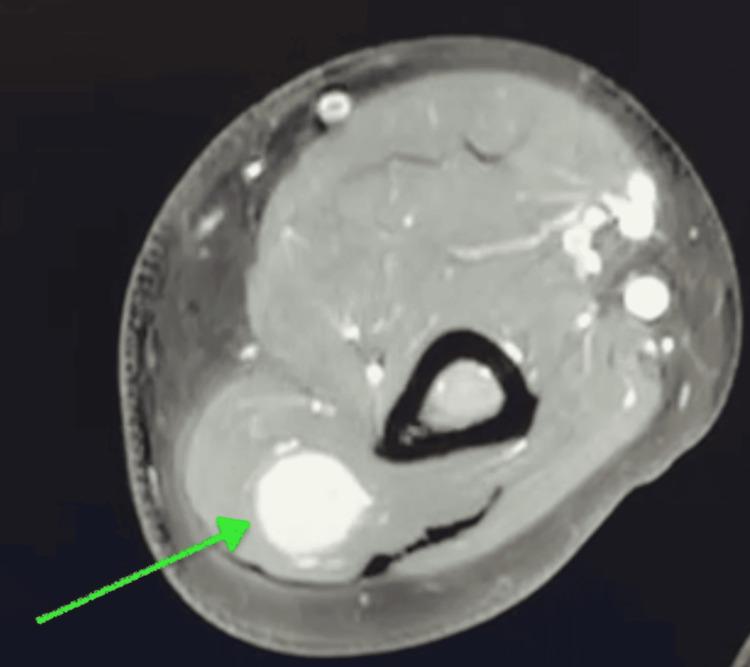

Schwannomas are uncommon, mostly benign nerve sheath tumors that typically present as painless or intermittently painful lumps. They are most commonly found on the flexor surfaces of the body, with occurrence in the radial nerve being exceptionally rare. We present the case of a 55-year-old male with a five-month history of a progressively enlarging, mobile mass on the posterior aspect of the right arm. The patient presented with a transient, "shock-like pain" that failed to respond to conservative management. Imaging confirmed a peripheral nerve schwannoma located deep in the triceps posterior fascia along the lateral head of the triceps within the radial nerve. Due to persistent symptoms and failure of conservative treatment, surgical excision of the neural tumor was recommended. This case highlights the clinical presentation and surgical management of a rare radial nerve schwannoma.

神经鞘瘤并不常见,大多为良性神经鞘膜肿瘤,通常表现为无痛或间歇性疼痛的肿块。它们最常见于身体的屈侧表面,在桡神经中出现极为罕见。我们报告一例55岁男性患者,其右臂后侧有一个进行性增大的可移动肿块,病史长达五个月。患者出现短暂的“电击样疼痛”,保守治疗无效。影像学检查证实为外周神经鞘瘤,位于桡神经内肱三头肌外侧头沿肱三头肌后筋膜深处。由于症状持续且保守治疗失败,建议手术切除神经肿瘤。本病例突出了罕见的桡神经鞘瘤的临床表现及手术治疗。